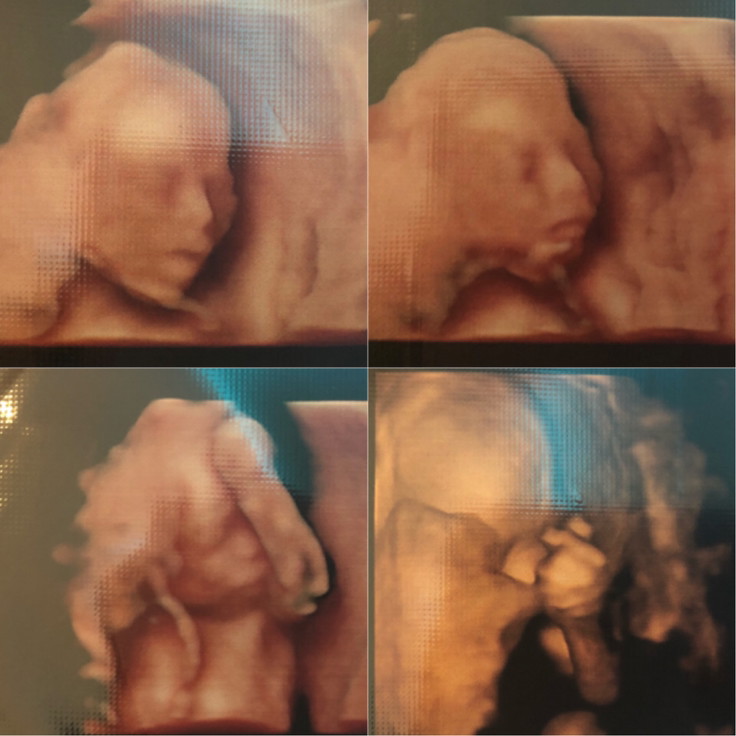

5 เดือนค่ะ 💛💛💛

5 เดือนค่ะ ลูกสาว👧

5เดือนจ้า❤️